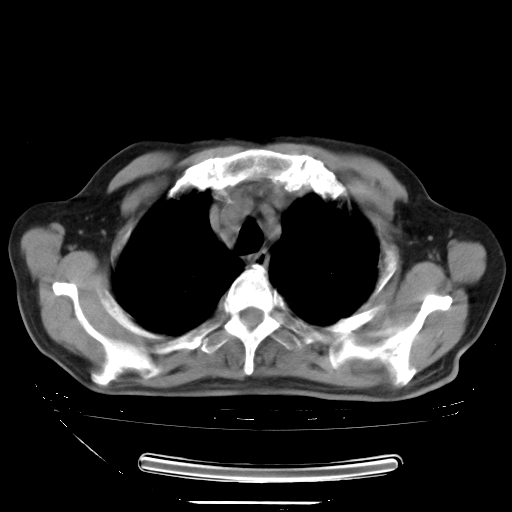

今天复查肺部CT,发现双肺广泛磨玻璃样改变。所以我把3月19日和5月9日相隔50天的肺部CT上传。请大家会诊。

2009年3月19日肺部CT片。

2009年3月19日肺部CT